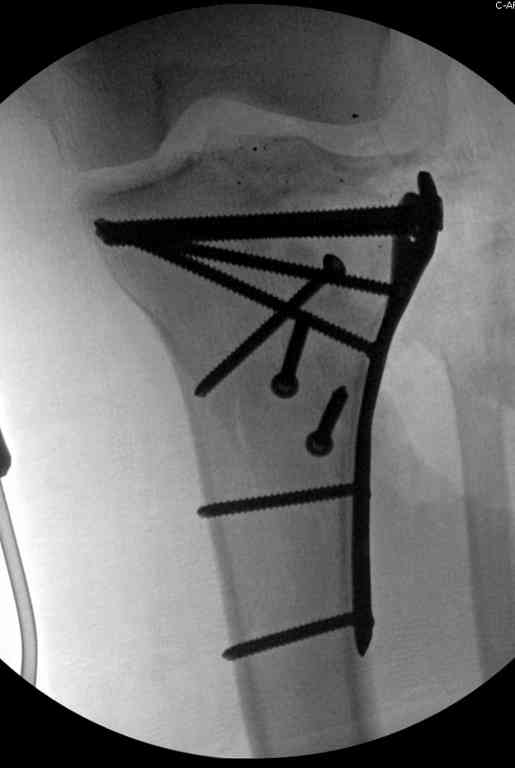

Здесь применение материала Plexur http://www.plexur.com для пластики при дефектах кости у больной с огнестрельной раной латерального тибиал плато с повреждением малоберцового нерва. Несмотря на интактный медиальный мышелок, для профилактики от вальгуса установлен АВФ и сделана ангиограмма.

После нескольких обработок и вакуумирования, поэтапно сделана фиксация тибиального бугра шурупами. И окончательную фиксацию закончили латеральной пластиной для тибиал плато и установкой пластического материала.

Для закрытия мягкотканых дефектов привлечена другая служба.